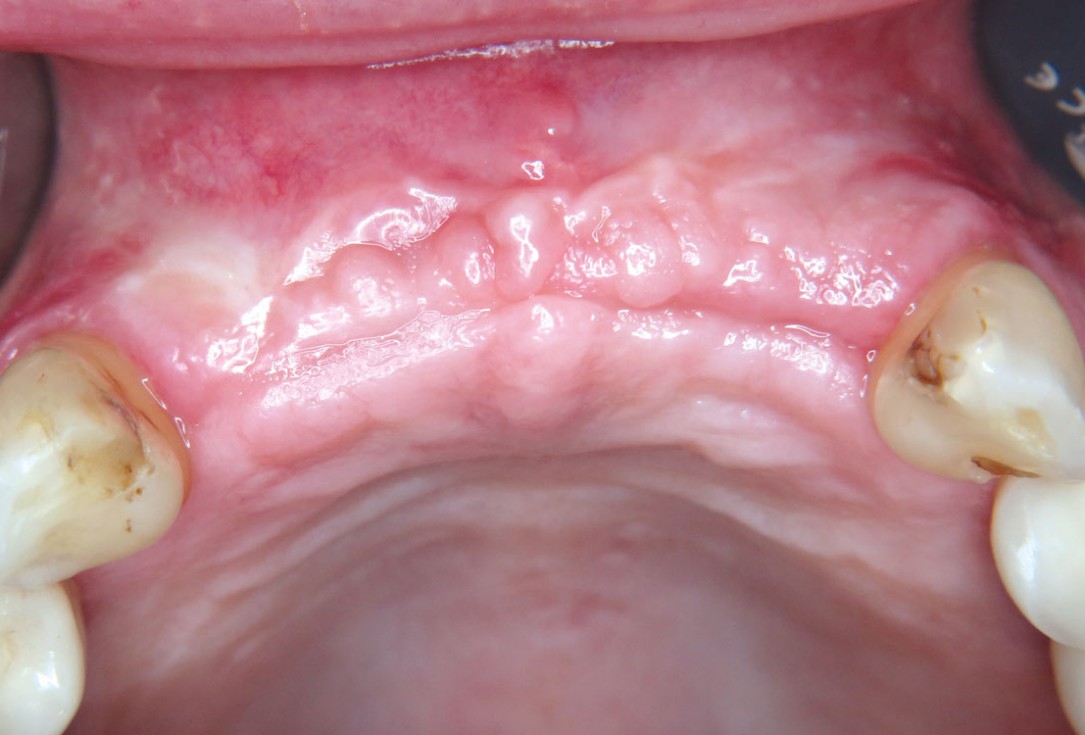

01 / 22 - Initial clinical situation – missing bonein regio 11, 12, 21, 22 and scarred soft tissue

Three-dimensional augmentation with maxgraft® cortico - M.Sc. E. Kapogianni